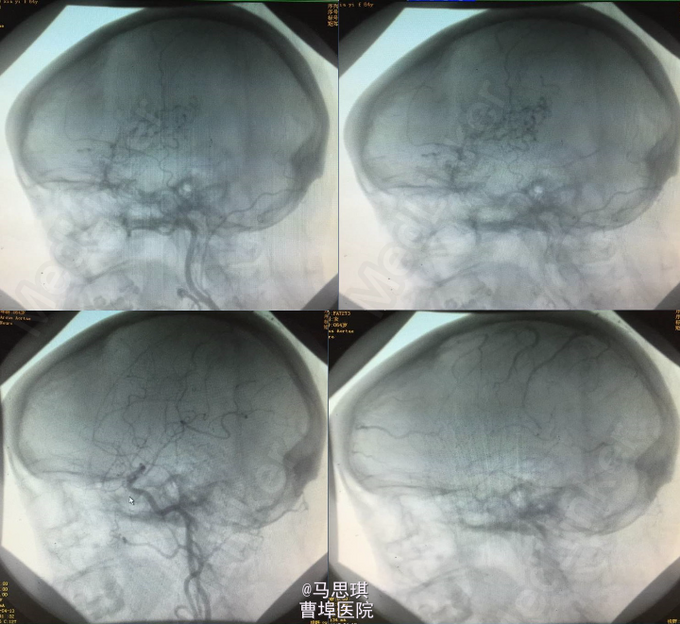

复查CT(3周后):左侧额颞顶叶片状脑梗塞密度较前片略降低。 3周后,患者行左侧脑膜中动脉血管畸形栓塞术,但因患者于部分供血血管造影时述左耳疼痛明显,放弃有明显临床症状供血血管栓塞术,随后出院。嘱氯吡格雷75mg Qd 立普妥 20mg qd 讨论:对于此类特殊病因的卒中患者如何评估溶栓风险?如何评估双抗风险?